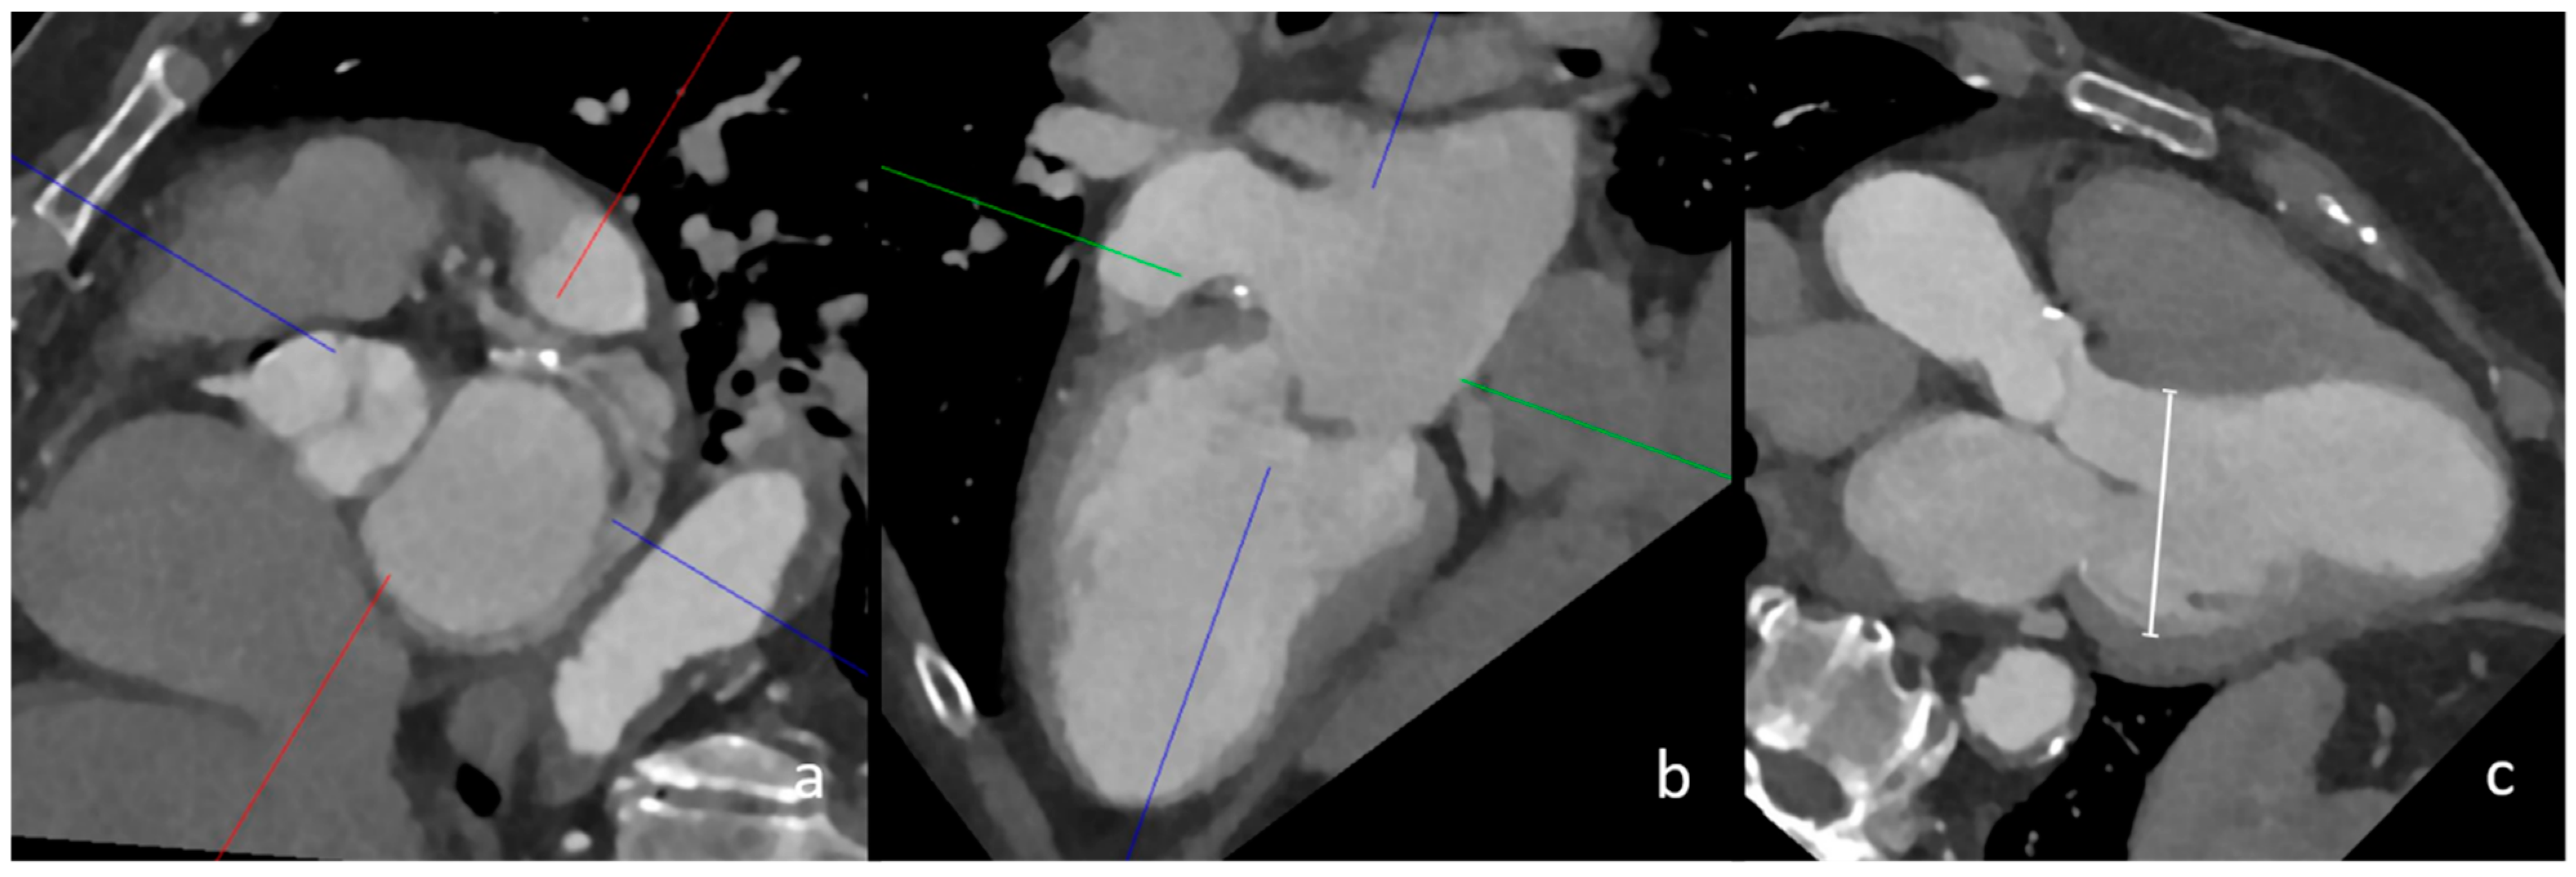

The cCT imaging was interpreted by two radiologists with several years of experience in cardiovascular imaging. The overall image and contrast quality was graded as (1) perfect, (2) good, (3) moderate or (4) non-diagnostic. Both radiologists assessed multiple cardiac imaging findings according to the recognised major and minor CES [1] (Supplementary Materials). In addition to the detection of atrial or ventricular thrombi, the presence of a left atrial septal pouch (LASP) and left atrial diverticulum (LAD), the configuration of the left atrial appendage (LAA; chicken wing, windsock, cauliflower and cactus), visual blood stasis in the LAA and the presence of interatrial contrast shunting as an indication of the presence of a persistent foramen ovale (PFO), the presence of valve implants, calcifications of the aortic and mitral valve, acute or previous myocardial infarction with or without ventricular aneurysms, cardiac tumours and the presence of left ventricular dilatation were assessed. The left ventricular diameters were approximatively measured in multiplanar reconstruction in a three-chamber view, as presented in Figure 1, following guidelines on chamber quantification, and a value of >53 mm in women and >59 mm in men was considered to indicate dilation [14]. Aortic arch atheroma was graded from 0 to 3, with grades 2 and 3 considered relevant (grade 1 = 0 to 4 mm plaque thickness, grade 2 ≥ 4 mm plaque thickness, grade 3 ≥ 4 mm plaque thickness with protrusion into the aorta; adapted from Tunick et al., 2000 and Amarenco et al., 1996 [15,16].

Figure 1.

CT measurement of left ventricular dilatation in three-chamber view. In this image, the multiplanar reconstruction angulation of cCT imaging (a,b) is depicted. The diameter of the left ventricle in this female patient was 56 mm, which confirmed left ventricular dilatation (image (c), white line).

4.1. Left Ventricular Dilatation

The strongest imaging risk factor among the known CES in our cohort was left ventricular dilatation measured in three-chamber view in multiplanar reconstruction (Figure 1). Left ventricular dilatation is a known risk factor for several cardiac diseases and has been associated with sudden cardiac death, among other complications [22]. Furthermore, geometric remodelling of the left ventricle has been shown to increase the risk of cardioembolic stroke and chronic heart failure [23]. In addition, left ventricular dilatation on cCT may indicate the presence of a dilated cardiomyopathy (DCM) [24]. In these patients, intraventricular congestion and thrombus formation are postulated to be promoted by reduced contractility and pump failure [25]. Furthermore, supraventricular and ventricular arrhythmias occur in up to 30% of patients with DCM, further increasing the thrombogenic potential [25]. In our exploratory analysis, the adjusted odds ratio of 32.4, with a remarkably wide confidence interval, suggests an association between left ventricular dilatation and a cardioembolic cause of stroke in patients with LVO; however, this needs to be further confirmed by studies with larger sample sizes.